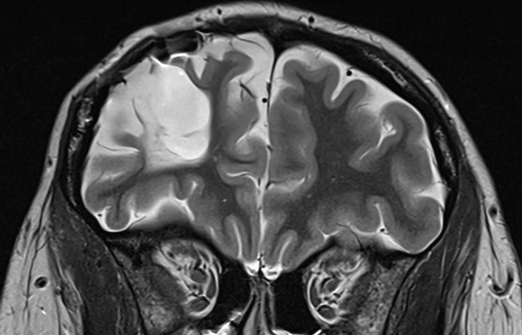

Feb 24, 2026Intellectually normal, traumatic brain injury at the age of 4 months, EEG is normal while awake. The MRI scan is reported to show extensive spongiosis and cavitation in the right frontal lobe. A colleague has treated the patient with lamotrigine for epilepsy for the past few years. He requested a review of the diagnosis.

3. The history provided by the patient and her boyfriend suggests that she either has left frontal lobe seizures or non-epileptic seizures or both. The MRI scan demonstrates an additional, potentially highly significant lesion in the left frontal lobe that was not mentioned in the report.